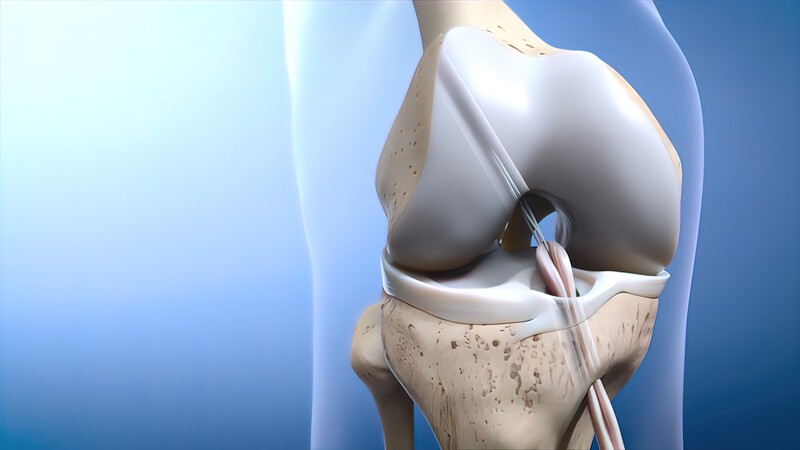

Biologic ACL Reconstruction Technique

What if you need to have an ACL operation? ACL surgery: Is it safe to get one?

ACL surgery has a high success rate when all the associated injuries are addressed in the same sitting by an experienced Arthroscopy surgeon Like any other surgery even ACL surgery has certain complications like Infection, failure or rerupture of the graft post injury but the complication in competent hands is less than 2%.

An ACL injury, ACL tear or other ligament tear knee or reasons for knee pain can be classified into three categories based on your MRI investigation and physical examination by Arthroscopic Sports Injury Specialist Surgeon:

Grade 1 ACL

Grade 2 ACL

Grade 3 ACL